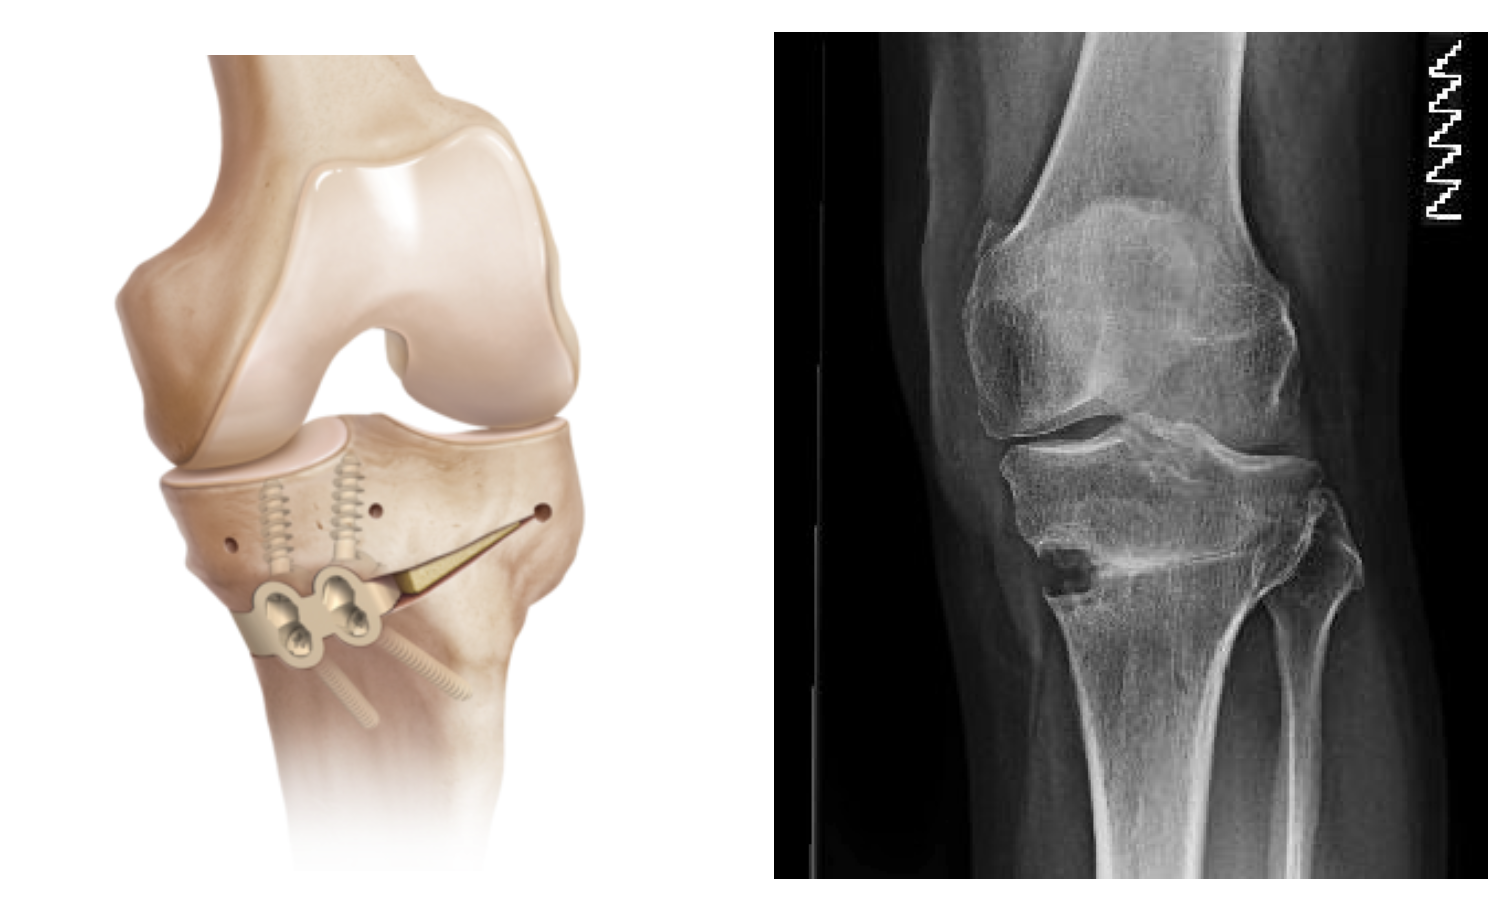

PARTIAL KNEE REPLACEMENT

" What a difference! Mr. Vioreanu is excellent."

After a year in pain and a previous faulty operation in which they removed a part of a cartilage essential for walking, my husband got a half a knee replacement.

HIGH TIBIAL OSTEOTOMY

I am now more active than I have been in many years

I had High Tibial Osteotomy surgery with Mr Mihai Vioreanu in November 2016. Having osteoarthritis in my left knee left me unable to enjoy a normal active life without pain if I spent long periods walking or standing.

"Enjoying an active life"

I had High Tibial Osteotomy surgery with Mr Mihai Vioreanu in February 2015. I had been in terrible pain with my knee in 2014 following arthroscopic 'clean-out' performed in a different hospital. Mr Vioreanu was excellent during all my consultations with him. He spoke openly and plainly about the surgical procedure in layman's terms. He thoroughly discussed all the pros and cons involved. Mihai was always ready and available to assist me after surgery. I am now back to a normal lifestyle and en